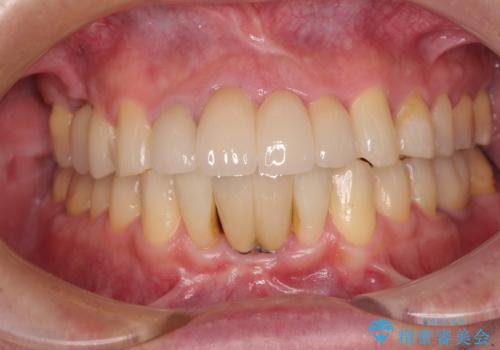

目立つ部分の銀歯や気になる変色歯をまとめてきれいに仕上げることができました。

割れてしまった奥歯をインプラントで 気になる銀歯もセラミッククラウンで審美的に